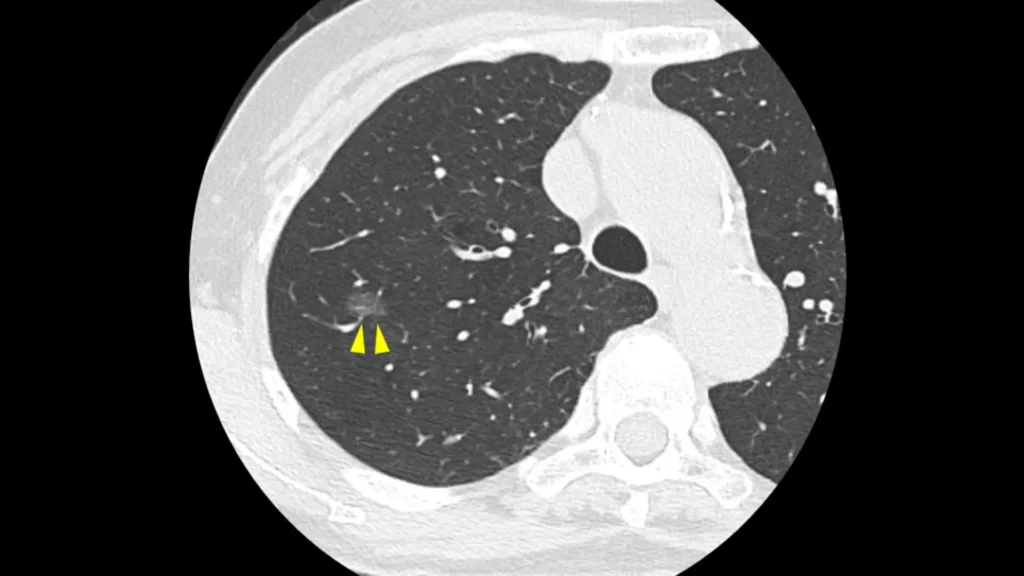

実際のCT画像所見

以下に

①:正常の肺

②:炎症の影

③:肺がん

④:③の患者さんのX線画像

を掲載します。

やはり、④のX線では肺がんを指摘するのは難しいですが、③でははっきり影がわかります。

ちなみにこの患者さんは、健診のX線では異常を指摘されませんでしたが、咳があったため心配で受診し、CTを撮ったところ肺がんが見つかりました。